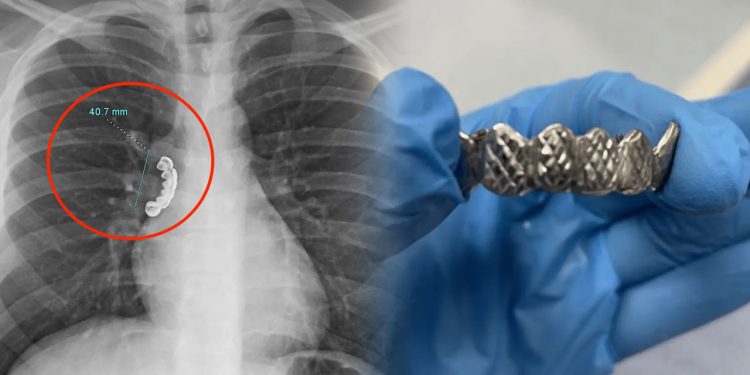

மருத்துவர்கள் அவரைப் பரிசோதித்த நிலையில், அவர் வாயில் அணிந்திருந்த 1.5 இன்ச் நீளமுள்ள அவரது பல்செட்டை அவர் விழுங்கியுள்ளார் என்று பின் தெரியவந்துள்ளது. அவரது நுரையீரலின் காற்றுப்பாதையில் அந்த பல்செட் நன்றாக சிக்கியிருந்துள்ளது.

பின்னர் மருத்துவர்கள் Bronchoscopy சிகிச்சை மூலம் வளையும் தன்மையுள்ள குழாயை அவரது வாய்வழியாக செலுத்தி நுரையீரலின் காற்றுப்பாதையில் சிக்கியிருந்த பல்செட்டை நீக்கியுள்ளனர். மூச்சுவிட கடும் சிரமப்பட்ட அந்நபர் சிக்கியிருந்த பல்செட் நீக்கப்பட்ட நிலையில், தற்சமயம் சீராக மூச்சுவிடுவதாக தெரிவிக்கப்பட்டது.